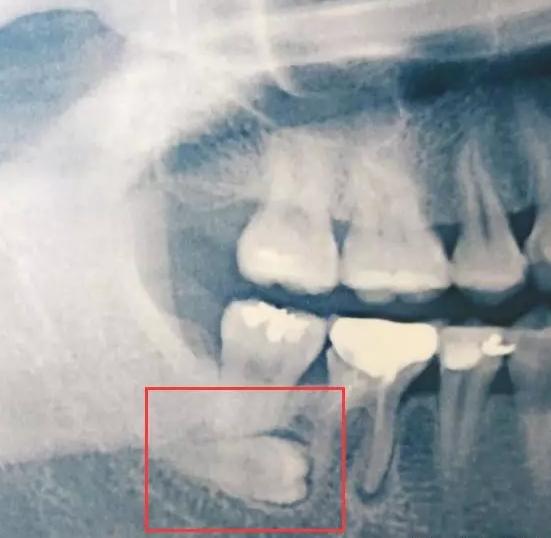

这几天,身边好几个朋友都去看牙了。他们说看牙前拍了个X光片,不拍不知道,一拍吓一跳,智齿有的躺着,有的斜着~

话说,你知道这样长的智齿在医学上叫阻生智齿吗?阻生牙不但会导致牙龈发炎疼痛,还可能会引起邻牙蛀牙,牙根吸收,甚至松动。因此,遇到这样的智齿就得拔!!!

3)阻生了,就是被前面牙挡住了,拔!